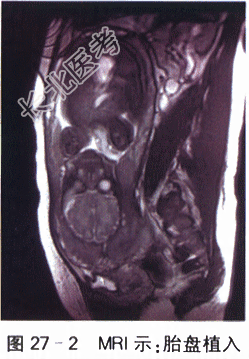

孕妇,34岁,因“G₄P₁,孕34⁺⁴周,凶险性前置胎盘,胎盘植入可能”入院待产。平素月经规则18,5/28天,量中,无痛经,LMP2022-6-20,EDC2023-3-27,停经30⁺天,查尿β-HCG(+),孕2月时出现轻微早孕反应(恶心、呕吐),孕5月出现胎动,胎动好,定期在外院做产前检查,无创DNA检查示低风险,早孕期B超检查提示胎盘边缘完全覆盖宫颈内口,植入不能排除;患者定期复查B超检查均提示前置胎盘,胎盘植入可能,孕期无阴道出血,孕32周MRI检查提示“植入性胎盘可能”;OGTT:4.46-10.35-8.79mmol/L,无多饮多尿多食,饮食控制后自测血糖均正常范围,产检尿酮(-);超声示胎儿发育与孕周相符。无外伤手术史,无高血压、心脏病、糖尿病等慢性疾病史。生育史1-0-3-1,2013年因羊水过少行剖宫产术,2014年末次人流。体格检查:神清,营养中等,无贫血貌,水肿(-),T37.0℃,P80次/min,R20次/min,BP110mmHg/70mmHg;心律齐,有力,各瓣膜听诊区未闻及杂音;双肺呼吸音清,未闻及干湿啰音;肝脾未触及,腹膨隆,神经系统(-)。产科检查:胎位LOA,胎动好;腹围95cm,宫高34cm胎儿体重估计2600g。骨盆测量:23-26-18-8.5(cm)。实验室和影像学检查:血Rt:WBC10.60×10⁹/L,N78.7%,Hb100g/L,PLT277.00×10⁹/L,肝肾功能指标、DIC、EKG等均正常。B超检查:胎盘位于子宫下段、完全覆盖宫颈内口,子宫下段前壁肌层尚可见,厚约6mm,与胎盘之间分界欠清,近宫颈内口处下段肌层局部血流丰富,似漩涡状(见图27-1)。MRI:完全性前置胎盘,伴胎盘植入。胎儿MRI未见明显异常(见图27-2)。